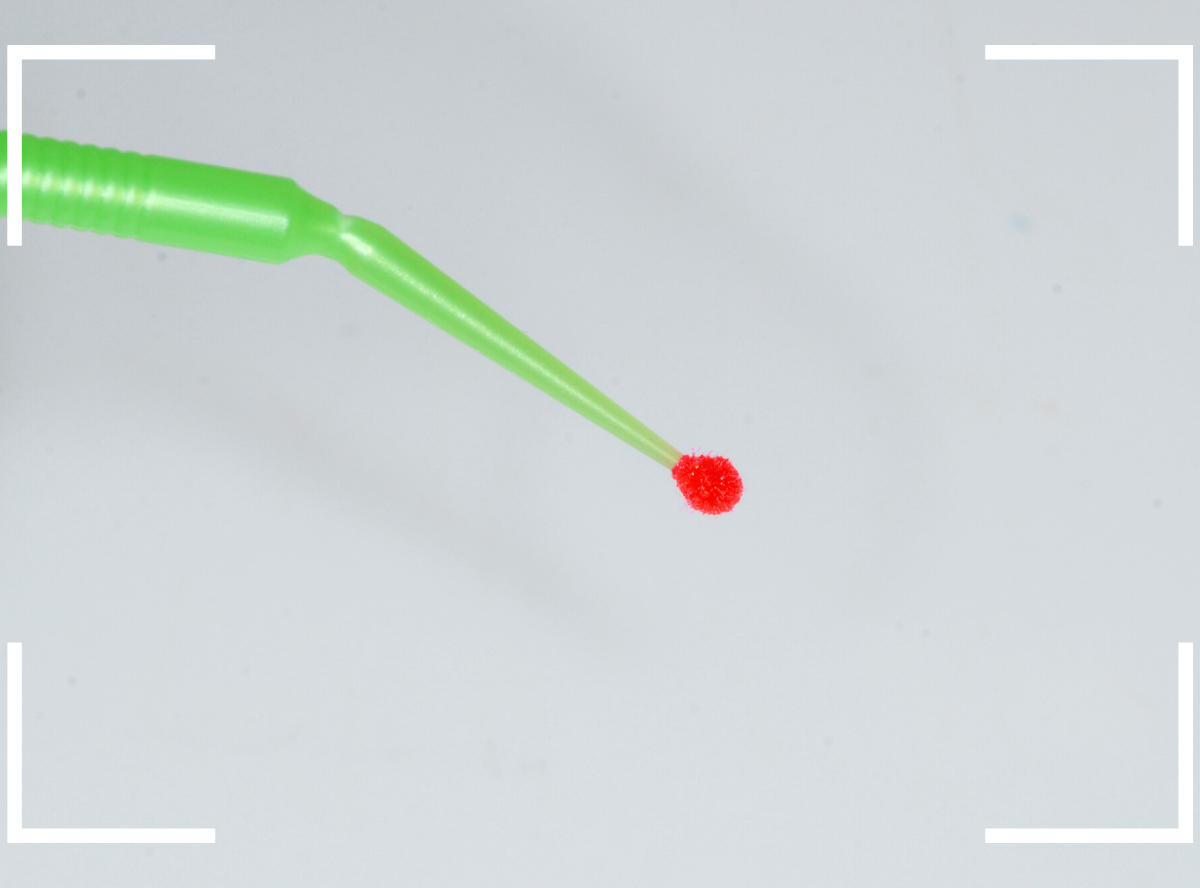

実際の検知液を使い方です。

ノズルをう蝕部に直接挿入して使うのが一般的ですが、それですとノズルの先端が汚染されてしまいます。

という事で、当院では使い捨てのアプリケーターを使い、ノズルが歯に直接触らないようにして使用しています。